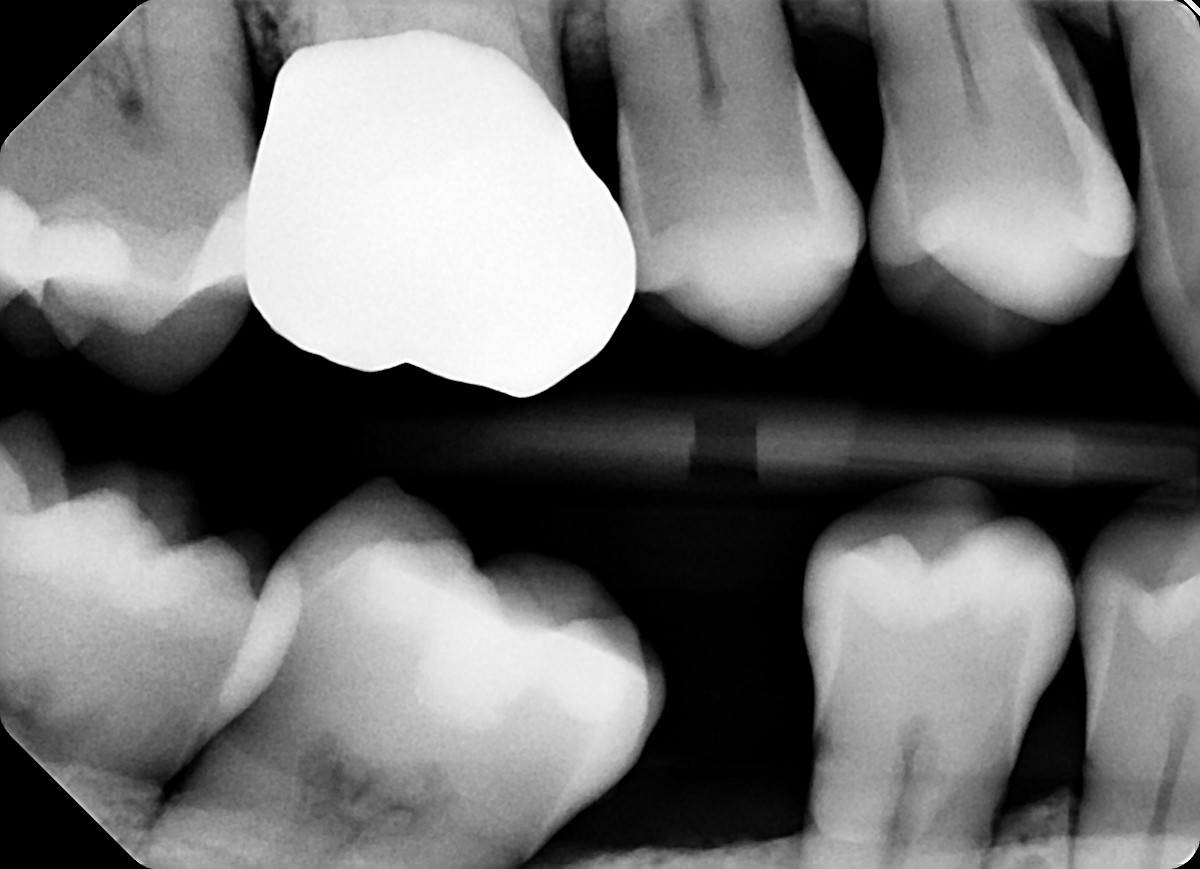

1. What option can explain the crown of the tooth # 1.4?